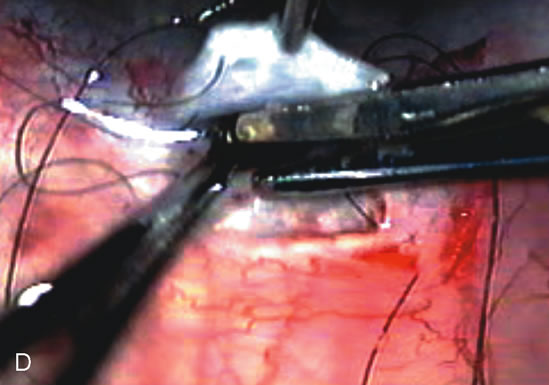

Fig. 4. Viscocanalostomy with deep sclerectomy and phacoemulsification. Nonpenetrating filtration procedures (NPFS) may be combined with phacoemulsification. Patients with mild disc damage and a history of limited topical drug therapy are the best candidates. Patients who require an IOP in the low teens are not good candidates for NPFS. By definition, NPFS is designed to lower IOP without penetrating into the anterior chamber, thereby avoiding the complications associated with trabeculectomy. Viscocanalostomy is intended to allow aqueous to percolate through a trabeculodescemetic membrane into a subscleral cavern created by the deep sclerectomy. The aqueous diffuses from the cavern into the dilated ostia of Schlemm's canal and into the episcleral venous plexus. A. Fashion a uniform 300-micron superficial scleral flap 1 mm into clear cornea. B. Construct a second 600-micron deep flap that facilitates the unroofing of Schlemm's canal, seen as the darker area. C. Use viscoelastic to dilate the ostia of Schlemm's canal. The major problem with viscocanalostomy is the eventual closure of the ostium decreasing flow to the episcleral plexus. D. Dissect the deep flap anteriorly into clear cornea creating the trabeculodescemetic membrane. This membrane is clearly seen between the scleral spur and the bend of the deep flap. The integrity of this membrane ensures the nonpenetrating portion of the surgery. Another problem with NPFS is the eventual fibrosis of this initially transparent membrane requiring goniopuncture. E. Deep sclerectomy gets its name from removal of the deep flap. Removal of this flap creates the potential subscleral space for accumulation of aqueous before it enters Schlemm's canal and exits the episcleral venous plexus. After removal of the deep flap, the superficial flap is sutured into place and conjunctiva closed. Approximately half of these procedures develop a shallow bleb.

Fig. 7. Phacotrabeculectomy adjacent to a failed filter in cataractous eye. The ability to combine small-incision cataract extraction with trabeculectomy all through the same incision adjacent to the failed filter allows the surgeon to work in a familiar superior area. Avoiding incisions into the existing bleb decreases conjunctival buttonholes, hypotony, operating room time, and subconjunctival bleeding. A. Appearance of failed bleb with exposure of superior temporal quadrant gained with a corneal traction suture. B. Prepare a limbus-based conjunctival flap and a scleral flap. C. This bleb is at high risk to fail again justifying the need for MMC, 0.2 mg/cc applied on a pledget for 4 minutes. D. Insert the keratome and perform phacotrabeculectomy in the usual fashion.